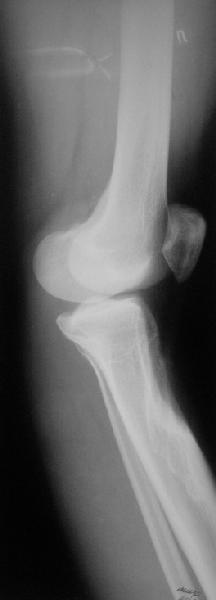

Продолжение обсуждения, начатого в октябре прошлого года (см. здесь) Наконец-то оперировали эту пациентку. Биопсию сделали - опухолевого ничего нет. Пока все участвовавшие в обследовании смежные специалисты и ортопеды сошлись, что это молокальная монооссальная фиброзная дисплазия. 20 марта наложили аппарат, сделали чрескожную остеотомию. К 3 апреля все докрутили. Сегодня заштифтовали. Начальные и итоговые снимки в приложении. Рекурвацию можно было еще немного больше устранить, и чуть кзади сместить диафиз. Но вроде и так ничего выглядит, по сравнению с тем, что было. Комментарии приветствуются.

ничего не понимаю в детской и ортопедии, но в боковой проекции нет рекурвации,

а даже немного гиперкоррекция, что по-моему есть хорошо. Кортикалы по задней стенке совпадают, диафиз на одну неправду кзади.